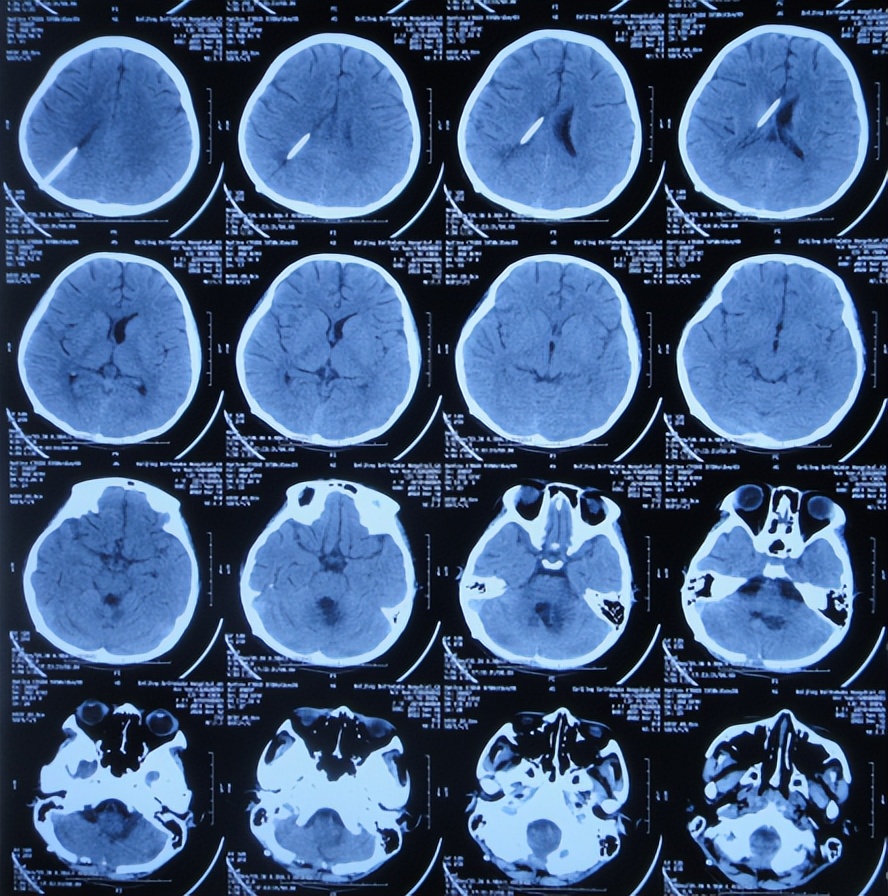

2022年10月16日(小脑出血当天晚上)住入李小勇脑脊液科。入院时:嗜睡,能被叫醒;时有恶心呕吐( 图-2 )。查头颅CT示小脑出血,脑室有扩张( 图-3 );肺部感染( 图-4 )。

图-3: 入院时颅脑CT晚上8点

但脑室腹壁外引流术后2天即2022年10月19日,患儿症状并未明显减轻,查颅脑核磁示脑室有缩小( 图-8 ),计划明日进行脑瘤切除术。

图-8: 2022年10月19日颅脑核磁增强

图-9: 2022年10月20日颅脑CT

2022年12月12日(住院治疗57天),颅脑CT示脑室引流术后状态( 图-15 ),给予夹闭引流管。

图-15: 2022年12月12日颅脑CT

但夹闭5天后即2022年12月17日,患儿出现不适,查颅脑CT示脑室有扩张( 图-16 ),打开引流管。

图-16: 2022年12月17日颅脑CT

2022年12月20日(住院治疗65天),查头颅CT示脑室缩小( 图-17 ),肺部CT示感染好转( 图-18 )。

图-17: 2022年12月20日颅脑CT

2023年1月9日(住院治疗85天即脑胶质瘤切除术后81天)出院,出院时:意识清楚,头痛恶心完全消失,自己走路不稳( 图-19 );出院时肺部感染变好、颅脑CT示无异常( 图-20 )。

图-20: 出院时颅脑CT